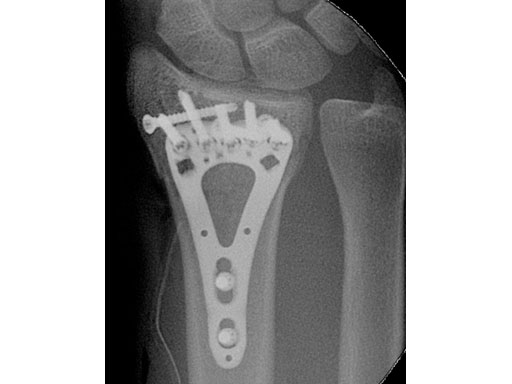

A young woman, 1,5 m tall, 45 kg, sustained a very distal C1.1 fracture of the distal radius.

Fig 2 Stabilization of the radiocarpal articular surface with one single 2.4 mm screw at the level of the watershed line, and narrow plate below the watershed line.

Fig 3ac Postoperative x-rays showing comparison of plate alternatives.

a Four-hole small.

c Five-hole.

Case provided by Martin Langer, Mnster, Germany